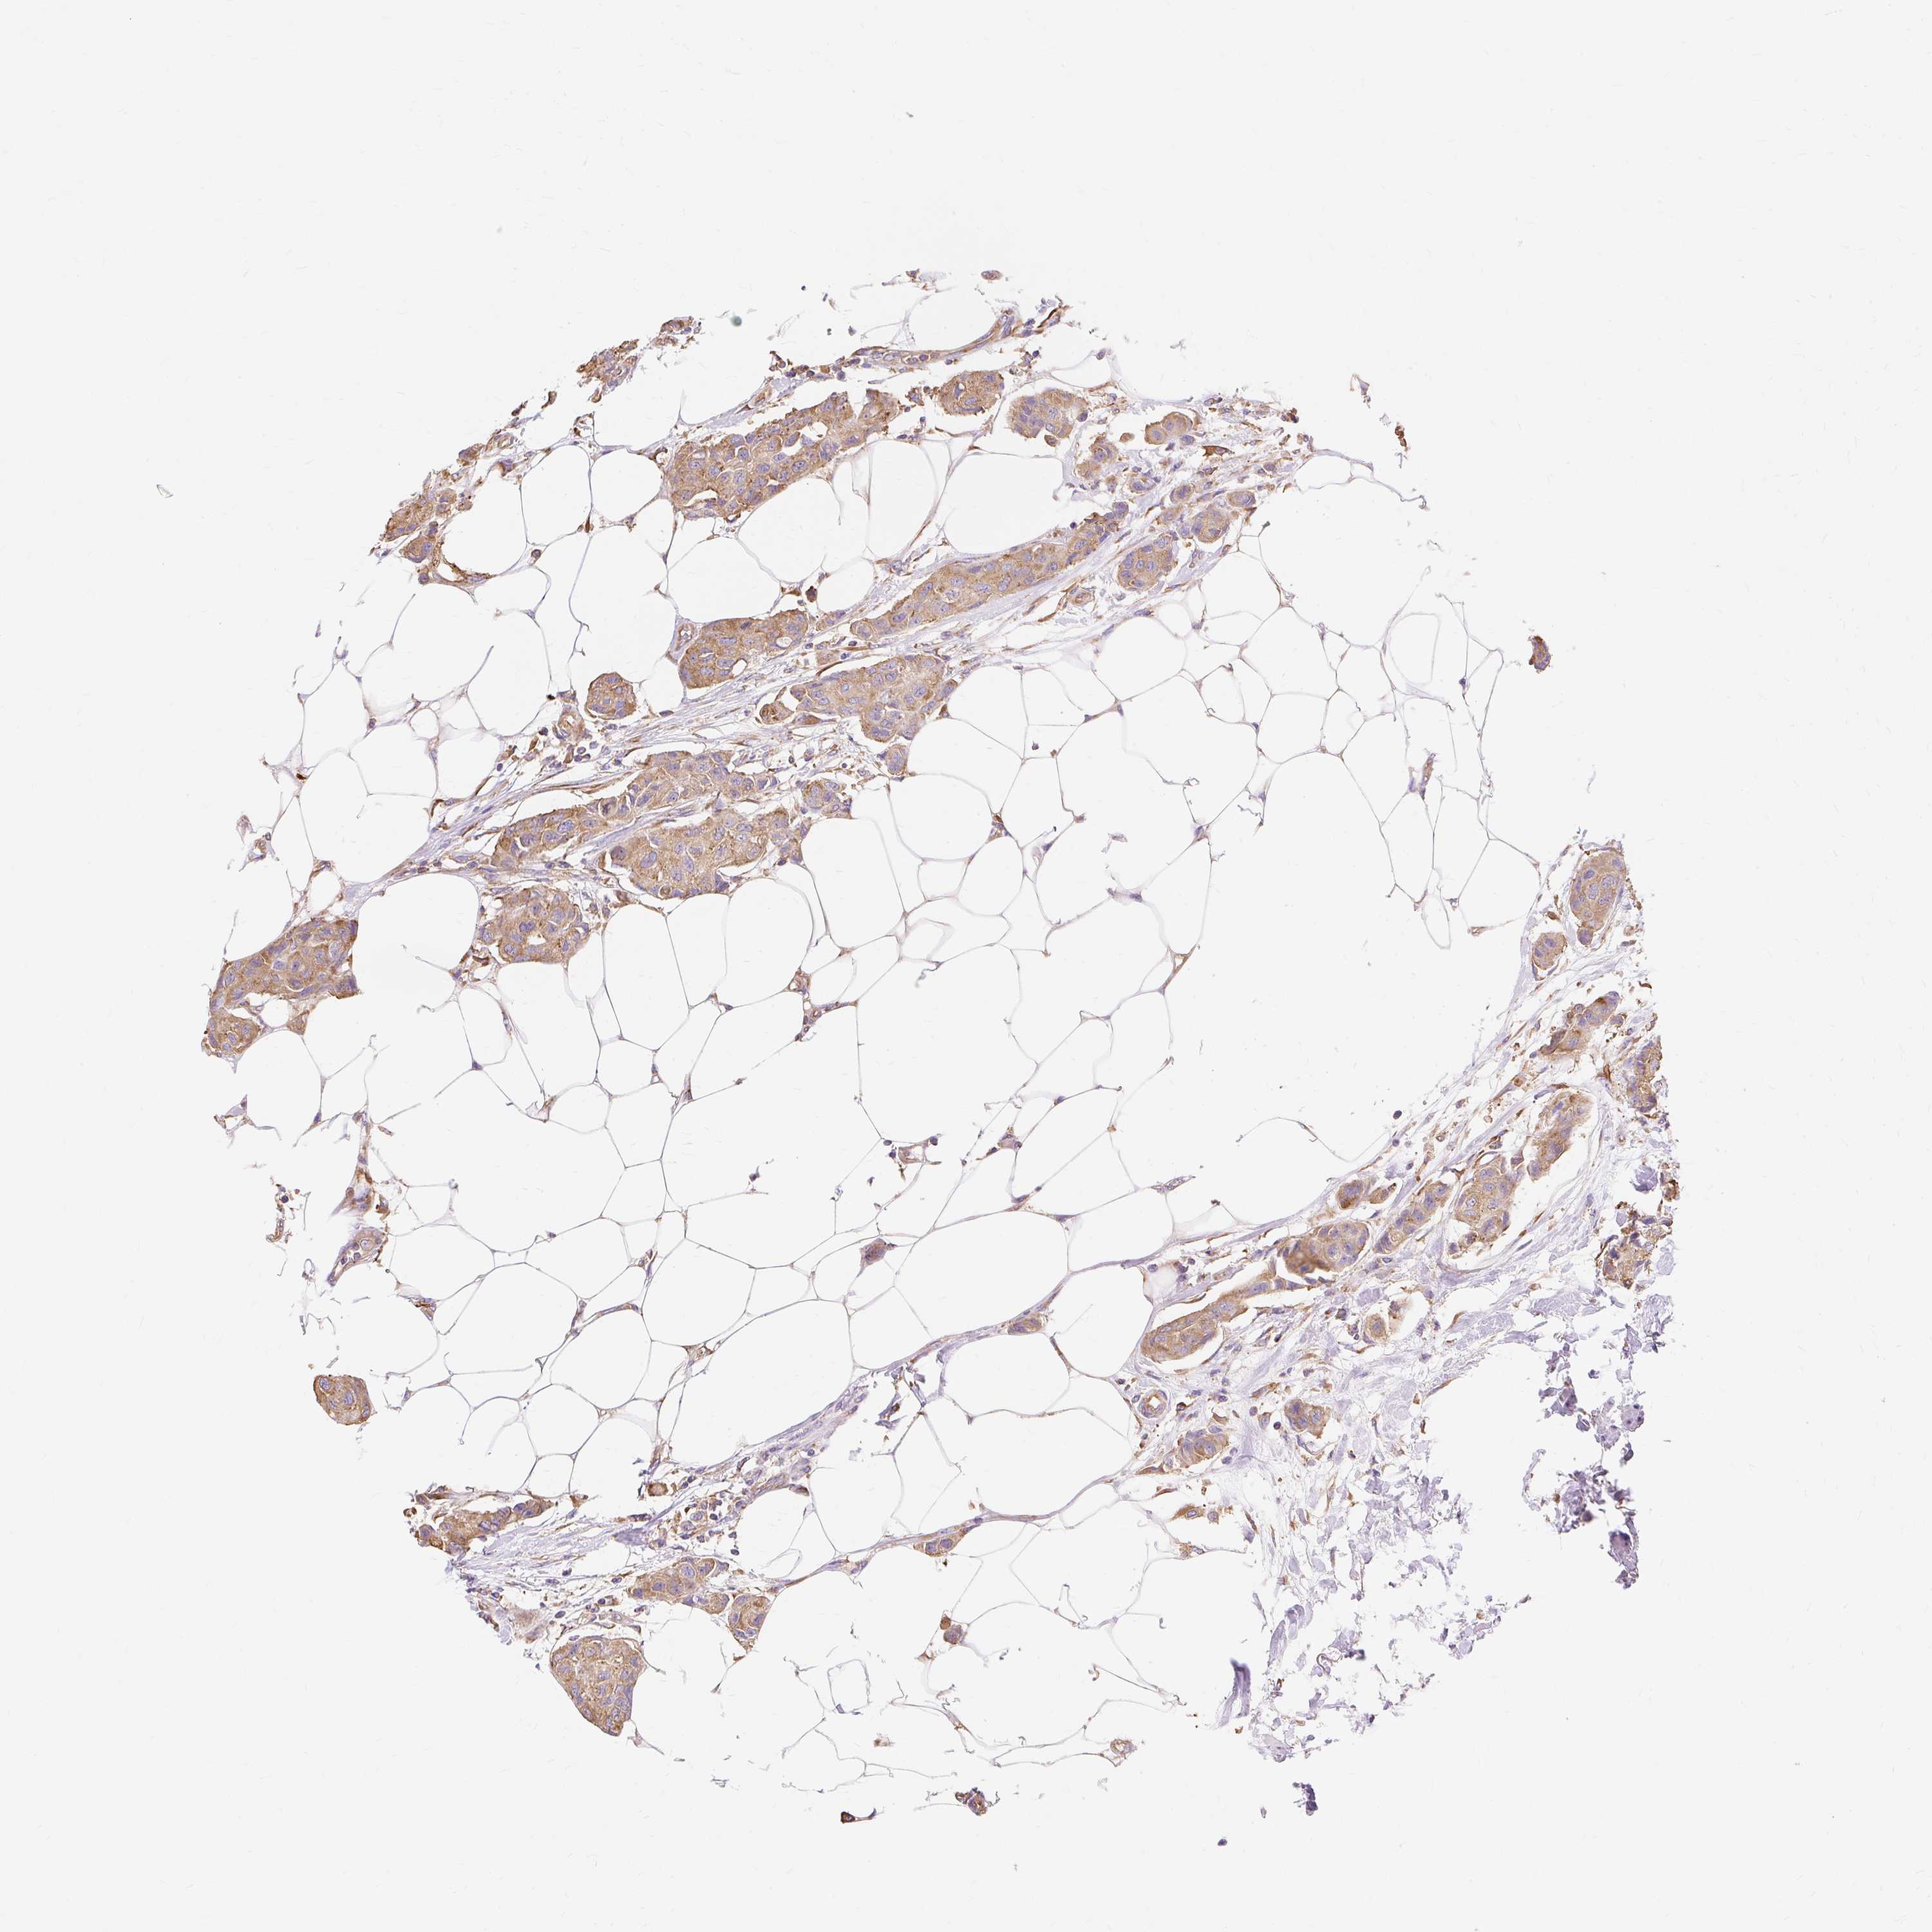

CANCER BREAST CANCER Show tissue menu

BRCA TCGA BRCA VALIDATION PROTEIN EXPRESSION